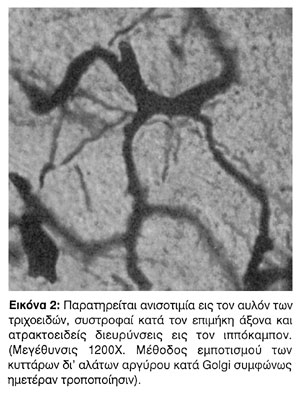

δ. Συστροφή των τριχοειδών κατά τον επιμήκη άξονα αυτών (Εικ.1, 2).

Περιοχαί, αι οποίαι εστερήθησαν της αρμονικής διαμορφώσεως των τριχοειδών είναι κυρίως ο ακουστικός φλοιός, ο ιππόκαμπος, ο οπτικός φλοιός, ο φλοιός του βρεγματικού λοβού, ο υπομέλας τόπος και ολογώτερον ο παρεγκεφαλιδικός φλοιός και ο οδοντωτός πυρήνας της παρεγκεφαλίδος. Αι πλέον άτυποι αγγειακαί διαμορφώσεις παρετηρήθησαν κυρίως εις τον ιππόκαμπον, εις την προρρινικήν περιοχήν και εις την προμετωπιαίαν περιοχήν. Ιδίως εις τον ιππόκαμπον παρατηρείται σημαντικός περιωρισμός των οριζοντίων τριχοειδικών κλάδων, οι οποίοι φέρονται παραλλήλως προς τον φλοιόν, πολλά δε από τα αγγεία φέρουν περιελίξεις και ανευρυσματικάς διατάσεις κατά τον επιμήκη άξονα αυτών.